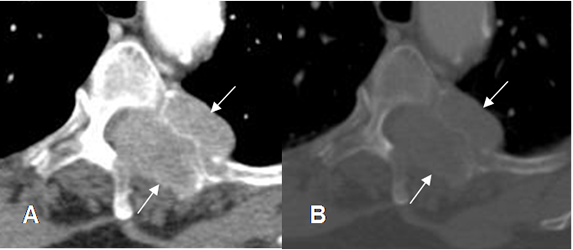

Fig 225. Metástasis líticas.

A: TAC axial en ventana de tejido y B: TAC axial en ventana osea. Lesión lítica que compromete los elementos posteriores en el lado izquierdo, por metástasis de neoplasia renal. Hay masa de tejidos blandos, que se extiende hacia el canal medular.